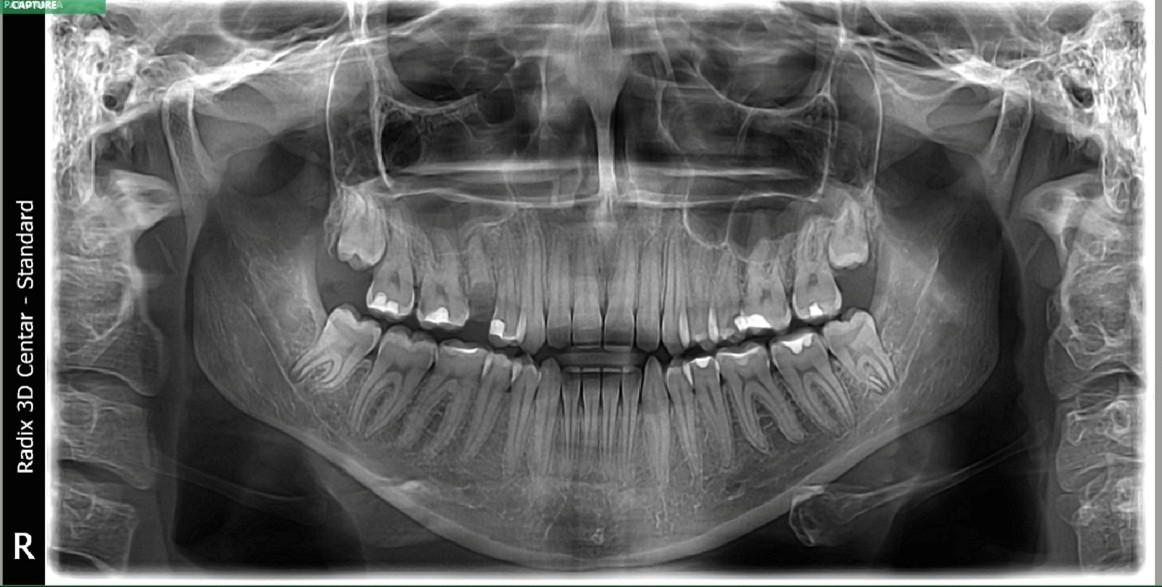

Zahvaljujući specijalnoj Magic Pan tehnologiji i senzoru velike rezolucije, ortapan snimci su znatno „oštriji" i „čistiji" u odnosu na klasične digitalne snimke. Snimci se obrađuju u EzDent softveru, i potom štampaju, ceo proces ne traje više od nekoliko minuta. Digitalni način snimanja na Vatech aparatu poslednje generacije podrazumeva vreme snimanja (ekspozicije) ispod 10 sekundi što za pacijenta znači kraću izloženost x zracima, a samim tim i manju apsorbovanu dozu za vreme snimanja.

Ortopantomogram je pregledna kružna rendgenska slika. Na njemu je vilica prikazana u potpunosti i raspoređena u ravnini...